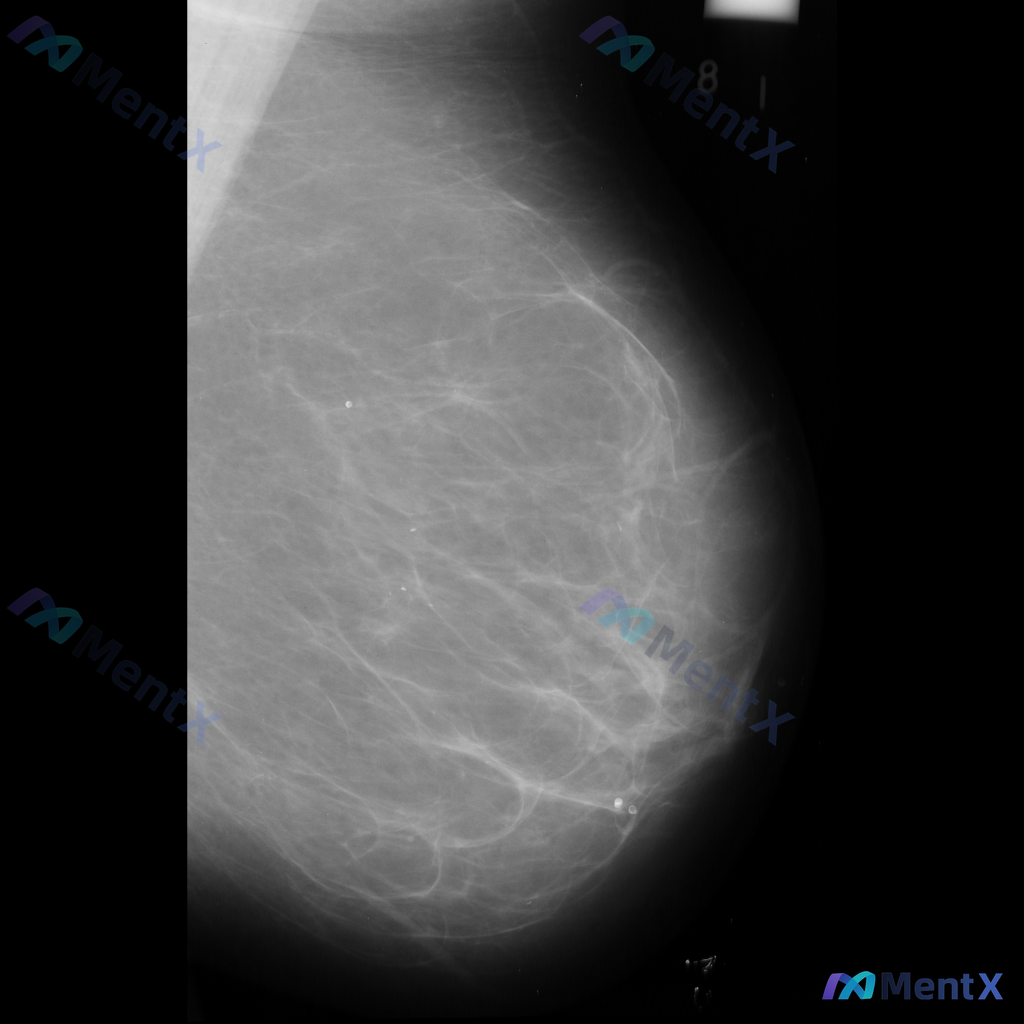

整理到一份单侧乳腺钼靶的影像资料,想和大家讨论一下读片思路: 影像背景与征象 - 背景:不均匀致密型乳腺 - 主要异常: 1. 乳腺中央及中下部可见一片边界模糊的斑片状/不规则形密度增高区 2. 该密度增高区域内,似乎存在乳腺正常小梁结构的牵拉或紊乱 3. 中下部偏乳头方向,有一组较为集中的、形态不...

整理到一张乳腺钼靶影像的讨论资料,先和大家同步一下读片可见的表现: - 背景为中等致密型乳腺 - 可见散在的细小钙化 - 乳腺下部近乳头区域有两枚圆形/卵圆形密度影,边缘清晰,内部伴有钙化 目前只有这一张影像,没有其他体位、既往片或临床病史补充。如果单看这组表现,你会先往哪个方向考虑?或者觉得最需要...